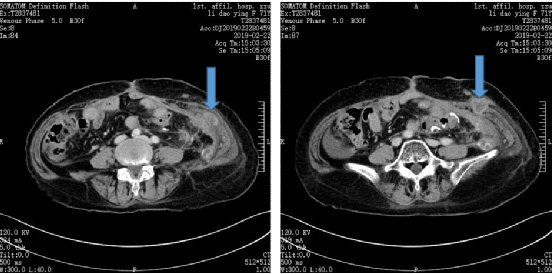

图5.2019年7月2日复查CT

患者在入组后两年内每2-3个月进行复查,CT结果均显示患者处于持续CR状态。用药期间未出现明显不良反应,每周进行皮下注射也十分方便,这也说明了恩沃利单抗在MSI-H/dMMR结直肠癌患者中出色的疗效和安全性。

图片

图6.2021年5月6日复查CT